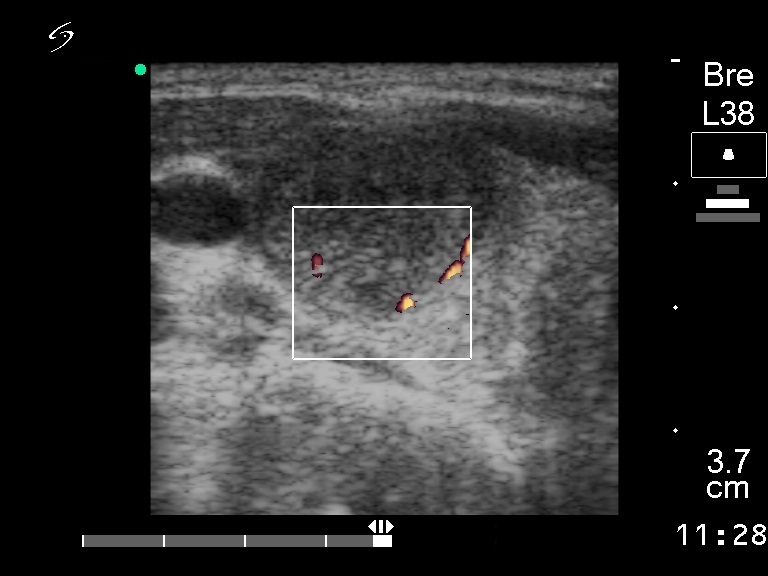

Ultrasonography: a solitary hypoechogenic nodule in the right lobe with a halo sign and perinodular blood flow.